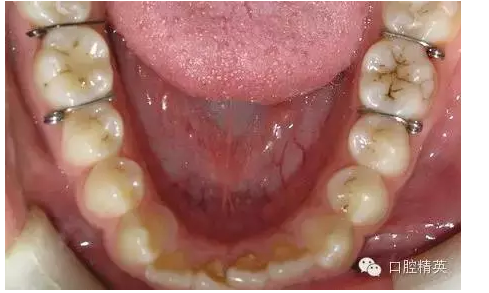

圖2

◆雖然目前正畸臨床上醫(yī)生多用彈力橡皮圈分牙,但當?shù)诙パ雷枭?,與第一磨牙鄰接不良時,或成人第一、第二磨牙鄰接太緊密時以及牙鄰面為面狀接觸的兩鄰牙者,則分牙簧是唯一能解決分牙問題的有效方法;正畸醫(yī)生應作為后備技術熟練掌握其應用技巧。

◆分牙簧各個口腔醫(yī)療器材商都有成品供應,但基本上是圖1形狀,即未激活狀態(tài),正確的使用方法是:在操作前用細絲鉗夾住簧圈處齦臂向內(nèi)彎折,使齦臂末端靠近合臂,形成角度(圖2),分牙時撐開,插入鄰牙間,利用兩臂的剪切彈力,產(chǎn)生間隙。

◆分牙簧分牙者,復診間隔時間不宜太長,以免鄰接點分開后,分牙簧脫落誤吞口內(nèi),一般3~4天即可,替牙期兒童尤應注意。另外,初學者還要留意支抗磨牙粘固帶環(huán)后分牙簧滯留于齦溝內(nèi),這個問題是進修醫(yī)生容易出錯的一個環(huán)節(jié),當鄰牙分開后,沒有見到分牙簧,不要主觀認為患者吐掉了,應常規(guī)檢查鄰接點齦乳頭齦溝處,確實沒有分牙簧再上帶環(huán)。